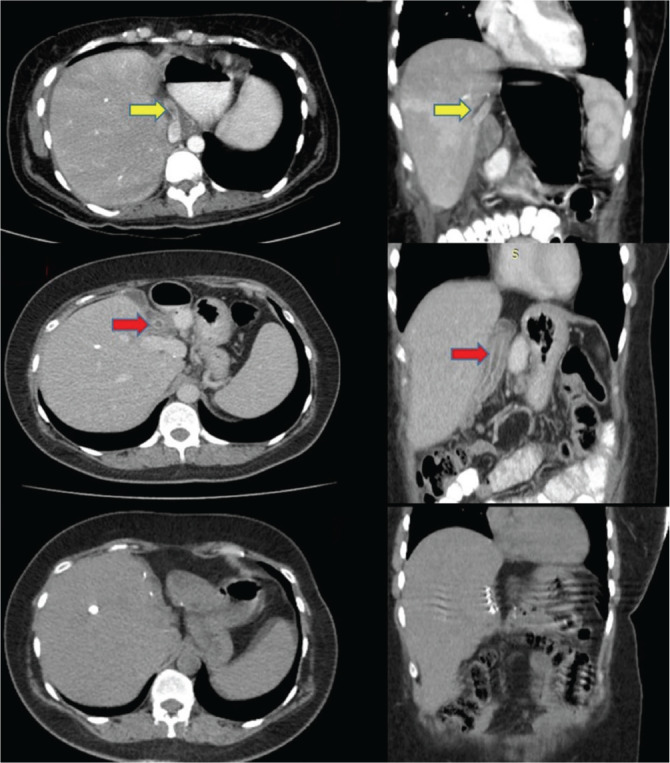

Living donor liver transplantation (LDLT) is a useful therapeutic option for end-stage liver disease due to the shortage of deceased donor liver grafts, particularly in Asia and Türkiye. Right liver LDLT is frequently performed in adults and some cases require anterior section venous drainage. Synthetic grafts, particularly expanded polytetrafluoroethylene (e-PTFE), are often preferred for venoplasties. Despite its many advantages, some complications associated with these grafts have been reported, such as gastrointestinal tract migration, perforation, and bleeding. Here we present an extremely rare case about an e-PTFE graft.